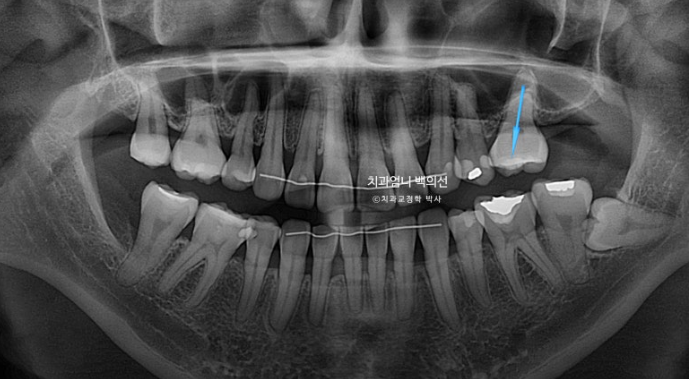

엑스레이상 좌측 위 첫번째 작은어금니 쪽으로 두번째 작은어금니가 쓰러지며 공간이 없어진게 보입니다.

어금니 교합관계 2급 입니다.

2급이었던 양측 어금니 교합관계는 비로소 1급이 되었습니다.

23.08~25.06

파란 화살표 임플란트가 들어가고 좌우 치아갯수가 맞아졌습니다. 덕분에 중심선도 개선하고 어금니 교합관계도 1급이 되었으며 앞니가 뒤로 쓰러진 옥니도 고칠 수 있었습니다.

1년 8개월에 걸친 재교정 기간동안 추가적인 치근흡수는 없었으며 치근 형행도는 처음보다 개선이 되었습니다.